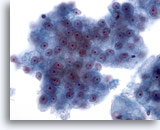

画像 2: 肝FNA – 良性肝細胞

反応性変化を来した良性肝細胞の集塊。細胞境界が明瞭な立方形の細胞が認められます。不透明な細胞質には空胞が認められるものもあれば、幾分顆粒状を呈するものもみられます。辺縁部は擦り切れた状態を呈しています。核はわずかに大小不同で、二核を有する細胞も認められます。小型の核小体がみられます。

40倍

画像 2

肝FNA – 良性肝細胞

反応性変化を来した良性肝細胞の集塊。細胞境界が明瞭な立方形の細胞が認められます。不透明な細胞質には空胞が認められるものもあれば、幾分顆粒状を呈するものもみられます。辺縁部は擦り切れた状態を呈しています。核はわずかに大小不同で、二核を有する細胞も認められます。小型の核小体がみられます。

40倍